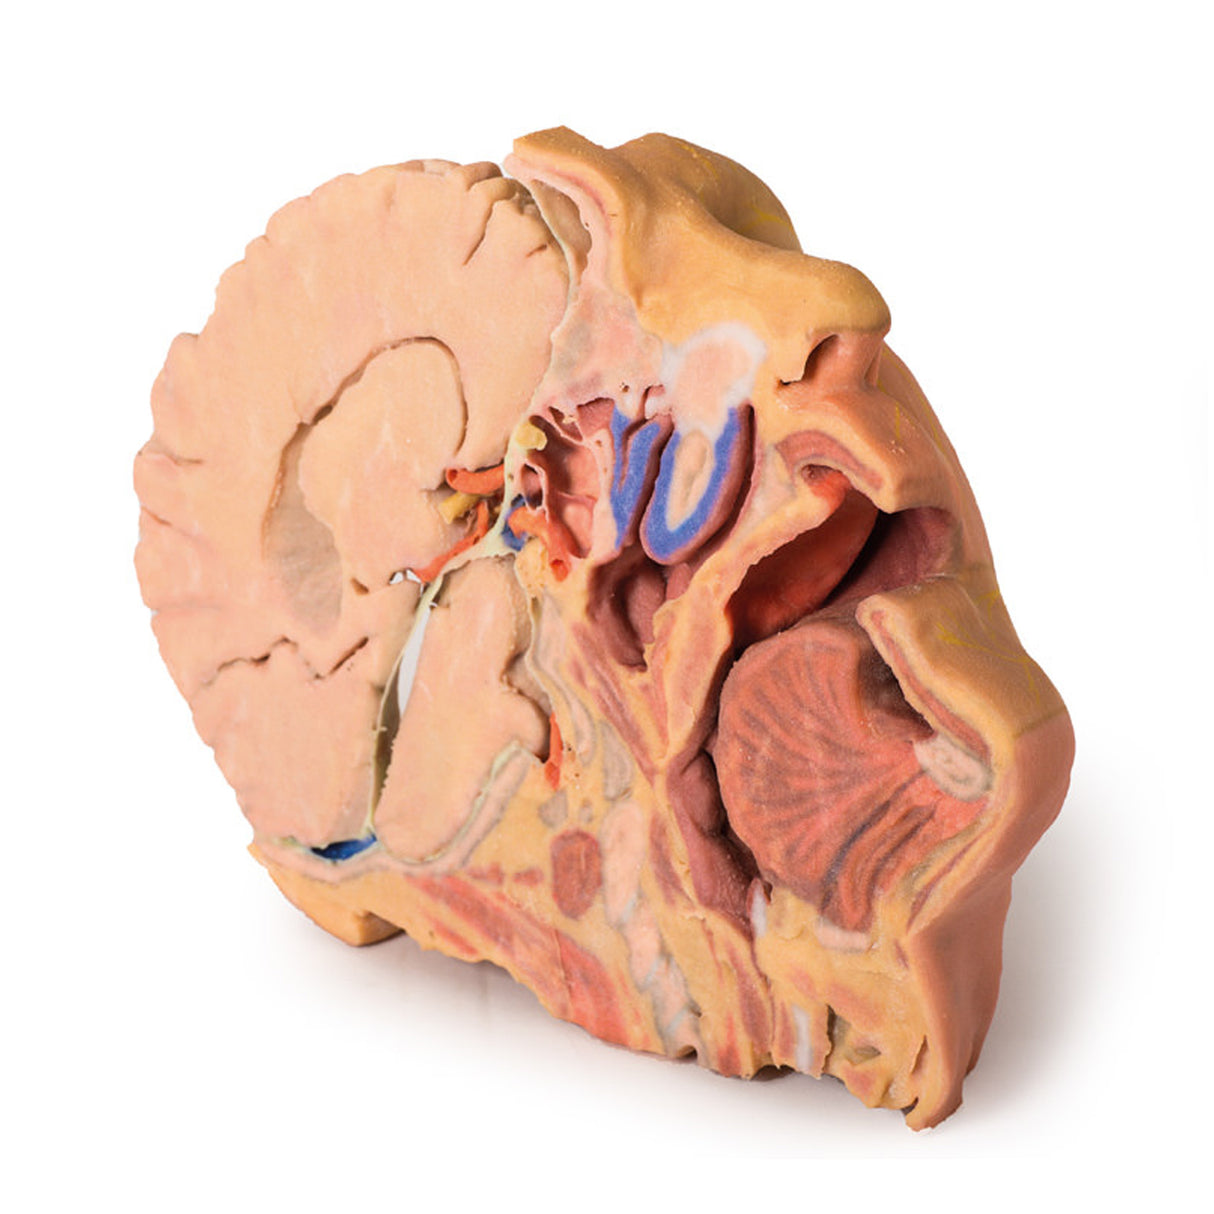

This 3D print provides a detailed view of head and neck anatomy, showing different structures depending on the perspective.

Brain and Cranial Cavity

The medial cerebrum shows the corpus callosum, thalamus, sulci, and gyri, while parts of the cerebellum are removed to expose the cranial fossae floor and fourth ventricle. The cavernous sinus, sella turcica, and intracranial course of cranial nerves II, III, V, VII–X, XI are displayed, including the facial canal and geniculate ganglion.

Medial Surface and Key Vessels

The parasagittal section reveals the lateral ventricle, cerebral peduncle, posterior cerebral artery, and the tentorium cerebelli. The internal carotid artery in the cavernous sinus is shown lateral to the optic chiasm. Additional structures include the mouth, tongue, associated muscles, nasal cavity, nasopharynx, and cervical vertebrae.